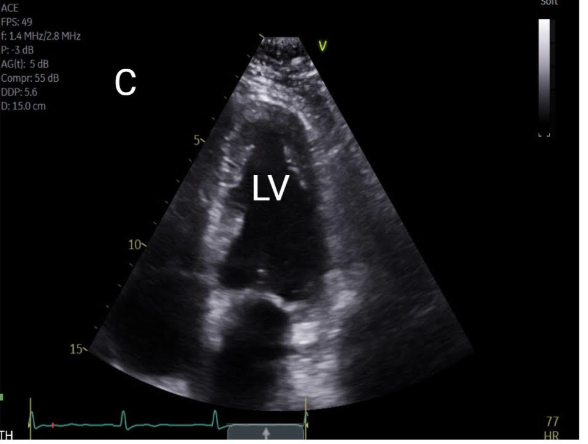

A 76-year-old woman with a significant smoking history presented with dizziness. Evaluation for syncope revealed normal orthostatic vitals and electrolytes. Electrocardiogram showed sinus bradycardia (heart rate 48 bpm) without QTc prolongation. Non-contrast CT of the head and CT angiography of the head and neck were unremarkable. Chest X-ray demonstrated left upper lobe atelectasis. Contrast-enhanced CT of the chest revealed bronchial obstruction in the left upper lobe and multiple pulmonary nodules in the right lung. Bronchoscopy identified a fungating mass obstructing the left upper lobe bronchus; biopsy confirmed adenocarcinoma. Transthoracic echocardiogram showed preserved left ventricular ejection fraction (60–65%), concentric hypertrophy, and grade I diastolic dysfunction. Cardiac MRI revealed a 3 cm mass along the basal anterior wall of the left ventricle with heterogeneous T2 signal intensity, consistent with myocardial metastasis. With a diagnosis of adenocarcinoma, the patient was advised to follow up as an outpatient for further oncologic management and advanced cardiac imaging.

This case highlights an incidental myocardial metastasis from lung adenocarcinoma in a patient presenting with bradycardia and dizziness, symptoms that may be related to cardiac involvement. While pericardial metastases are more common, myocardial infiltration is rare and often asymptomatic. Cardiac spread may occur via hematogenous, lymphatic, or transvenous routes and can present with arrhythmias, effusions, or hemodynamic compromise. Echocardiography is useful for initial evaluation, but cardiac MRI provides superior detail in assessing lesion characteristics and differentiating tumor from thrombus. Multimodal imaging plays a key role in identifying occult cardiac metastases that may impact clinical management.